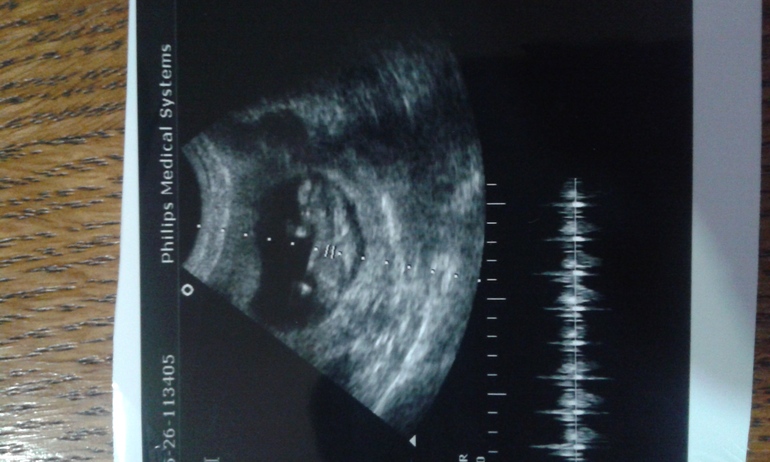

12+4 недель

УЗИ, КТГ, доплерСходила на приём сегодня.врач быстро сделала узи,убедится что ребёнок растёт.ничего не сказала.только то что всё хорошо.большое узи на след недели.там всё объяснят.а пока есть снимок.кто разбирается,подскажите:5.6 это размер малыша?и что означают другие значения.маленького видела,помахал мне ручкой,пнул ножкой.шустренький.

Про другие значения ничего не знаю, а 5,6 это да, размер от копчика до темечка- ктр. Я позавчера ходила в 12+3 примерно такой же размер - 5,8

5.6 скорее всего да, ктр)))) даже не верится что через неделю мне моего малыша такого же размера уже покажуи